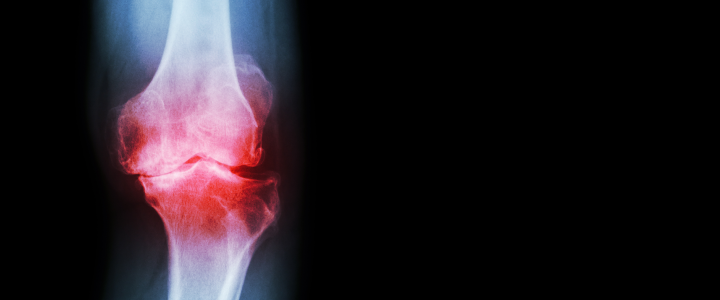

Knee osteoarthritis, most often referred to as knee pain, is the most common joint disease and a significant cause of knee pain. This limiting condition describes the progressive degeneration of the joint cartilage, which acts as a natural cushioning absorbing the shocks and providing a smooth, gliding surface. Once the cartilage wears out, the bones rub together closely, causing pain, swelling, and stiffness. Considering that knee osteoarthritis is a degenerative pathology, it is impossible to return to a pre-injury state. However, radial shock wave therapy and other methods allow you to reduce pain and improve function effectively, and in turn, substantially improve your quality of life.

image of healthy joint vs. osteoarthritis